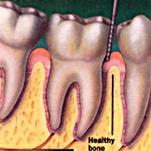

În ultimii 25 de ani s-au înregistrat progrese remarcabile în tratamentul parodontopatiilor marginale mai ales în zona regenerarii parodontale si osoase, teorie sustinuta de ipoteza conform careia celulele progenitoare din ligamentele parodontale sunt capabile sa regenereze sistemul ligamentar de sustinere parodontala (Melcher - 1976).

Majoritatea tratamentelor care aveau la baza aceasta ipoteza foloseau membrane-bariera pentru regenerarea tisulara dirijata (guided tissue regeneration - GTR) cu rol de a selecta si spori anumite populatii celulare si de a stimula apozitia coronara de ligamente si de cement pe suprafetele radiculare denudate. Ulterior, utilizarea grefelor os 24524m1214y oase (autogrefe, alogrefe, xenogrefe) si a conditionarii suprafetei radiculare cu acid citric a adus noi evidente histologice în explicarea procesului de regenerare tisulara. Vindecarea plagilor parodontale dupa aceste procedee este de tipul noii insertii si nu prin regenerare parodontala (vezi tabel).

S-a demonstrat ca proteinele cu origine în teaca radiculara Hertwig au un rol crucial în formarea cementului radicular acelular din cursul dezvoltarii radacinii dentare. Aceste proteine accelereaza formarea de ligamente parodontale si os alveolar în cursul embriogenezei. De aceea, administrarea de astfel de proteine exogene care se regasesc si în matricea smaltului dentar, ar avea un efect terapeutic regenerativ.

PrefGel este un gel conditionant cu pH neutru (EDTA 24% în gel de carboximetil celuloza) care îndeparteaza "smear layer"-ul restant pe suprafata radiculara dupa îndepartarea mecanica a tesutului de granulatie, placii bacteriene si a tartrului dentar, eliminarea acestui "smear layer" asigurând interactiunea si precipitarea EMD pe suprafata radiculara curata. Aceasta interactiune este vitala pentru regenerarea parodontala care include formarea de cement, ligamente parodontale cu fibre de colagen orientate functional si de os alveolar.